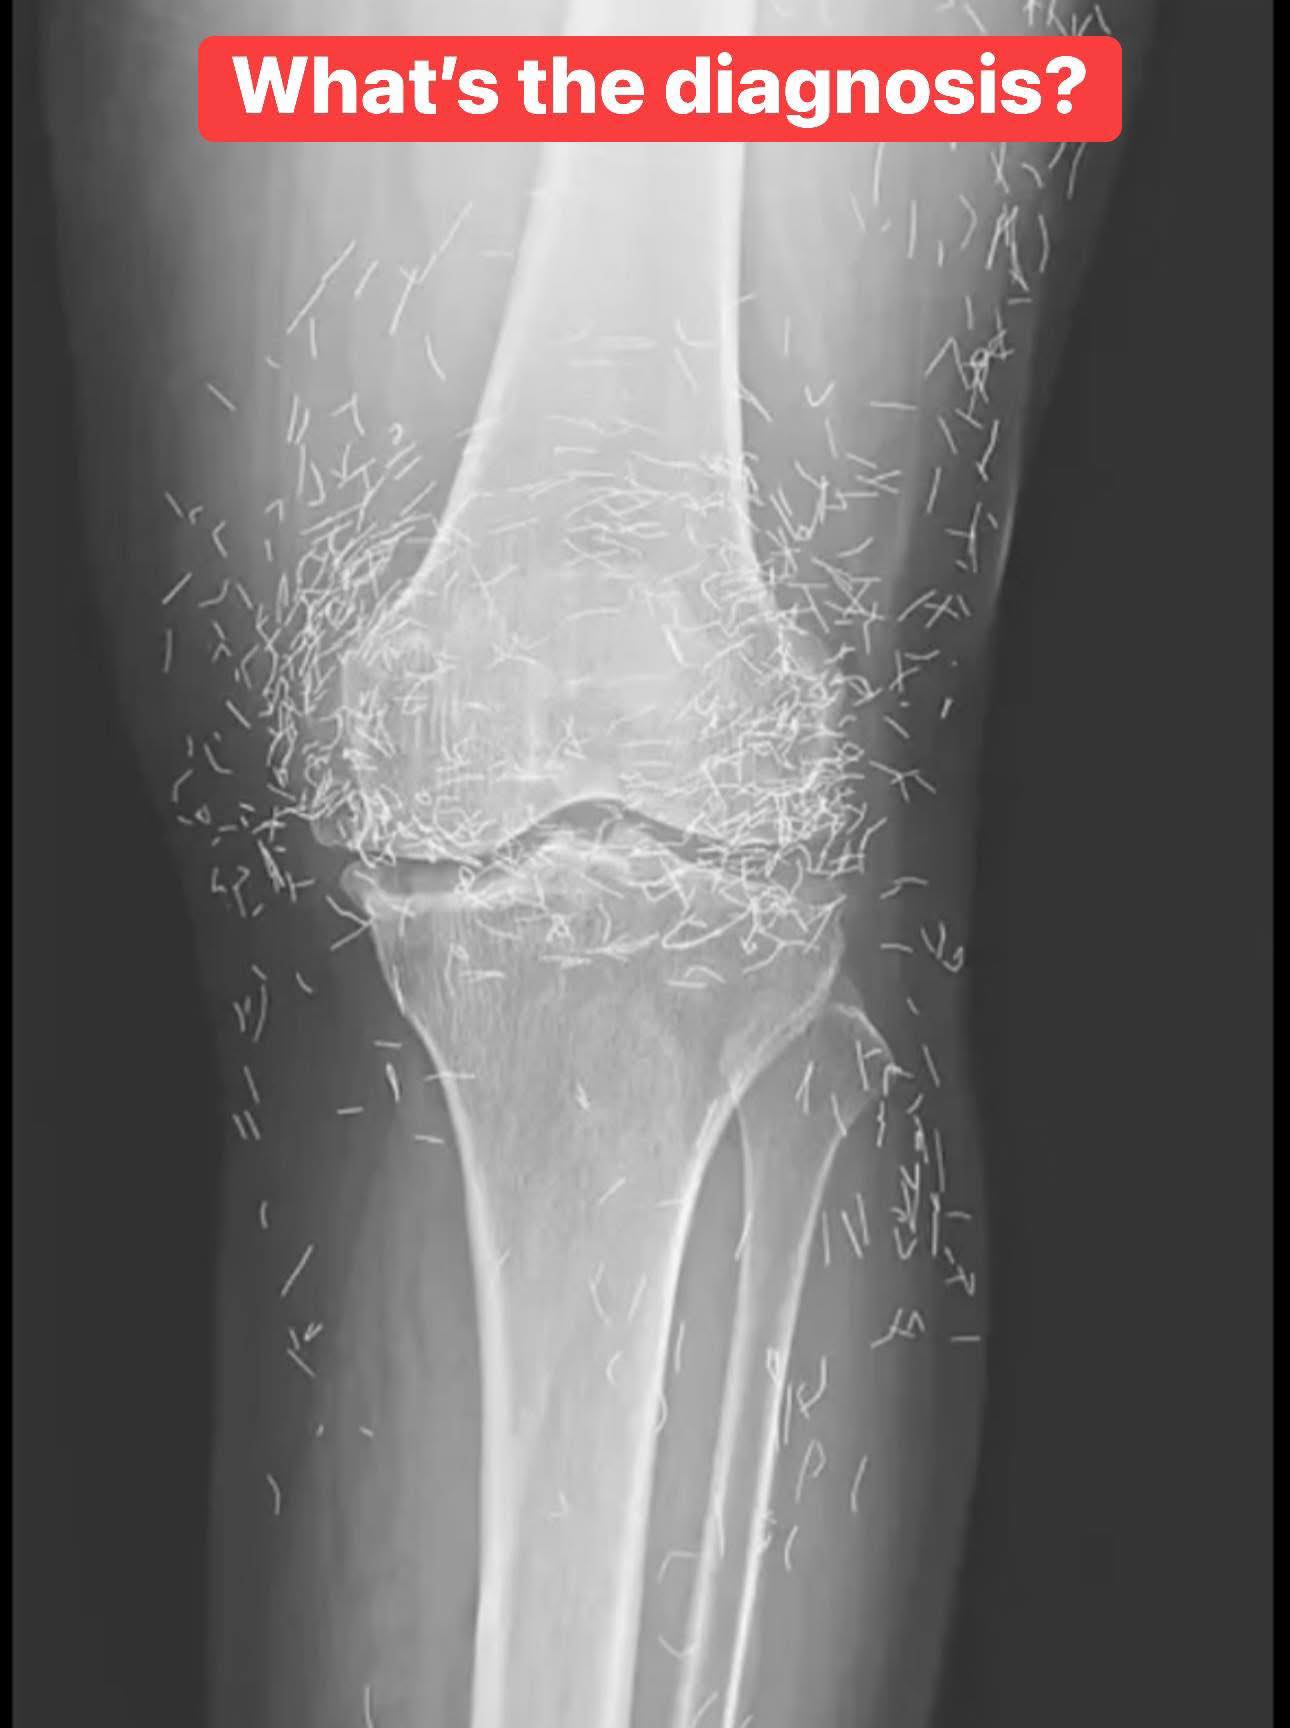

When a 65-year-old South Korean woman went in for knee pain, doctors weren’t expecting to strike gold. But that’s exactly what they found. Unwanted stomach issues Living with osteoarthritis can be incredibly challenging. The condition gradually wears down the cartilage in your joints, leading to stiffness, swelling, and persistent pain that can make even simple … Read more